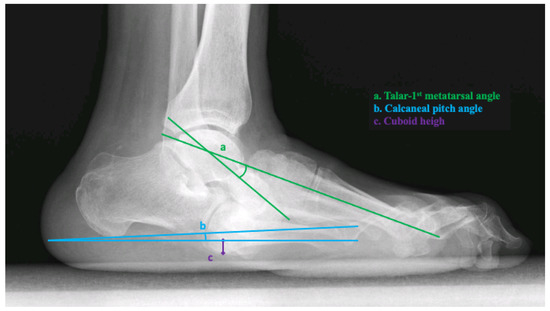

The three most reliable radiographic measures to assess for foot ulceration were performed by digital radiographs in the lateral view, including the lateral talar-first metatarsal angle, calcaneal pitch, and cuboid height [11,12]. All radiographic measurements were taken from the weight-bearing position at baseline [16].

The lateral talar-first metatarsal angle was measured as the angle formed from a line bisecting the talar body and neck and a line bisecting the first metatarsal. Apex plantar angulation was considered a negative angle [16]. The calcaneal pitch was measured as the angle between the reference line from the plantar aspect of the calcaneal tuberosity to the plantar aspect of the fifth metatarsal head and a line extending from the most plantar aspect of the calcaneal tuberosity to the most plantar aspect of the anterior process of the calcaneus. Cuboid height was measured as the perpendicular distance from the plantar aspect of the cuboid to a line drawn from the plantar aspect of the calcaneal tuberosity to the plantar aspect of the fifth metatarsal head. The distance was measured in millimeters and was negative if the plantar cuboid was plantar to this line [16] (Figure 1). Two trained clinicians with more than 5 years of experience treating diabetic foot complications analyzed and extracted data from each radiographic measurement and calculated the average angle. Both investigators who analyzed and extracted data from radiographic angles were blinded to the clinical data from every patient.

Figure 1. Radiographic measurements in the weight-bearing lateral X-ray. Legend. a, talar-first metatarsal angle (°); b, calcaneal pitch angle (°); c, cuboid height (mm).